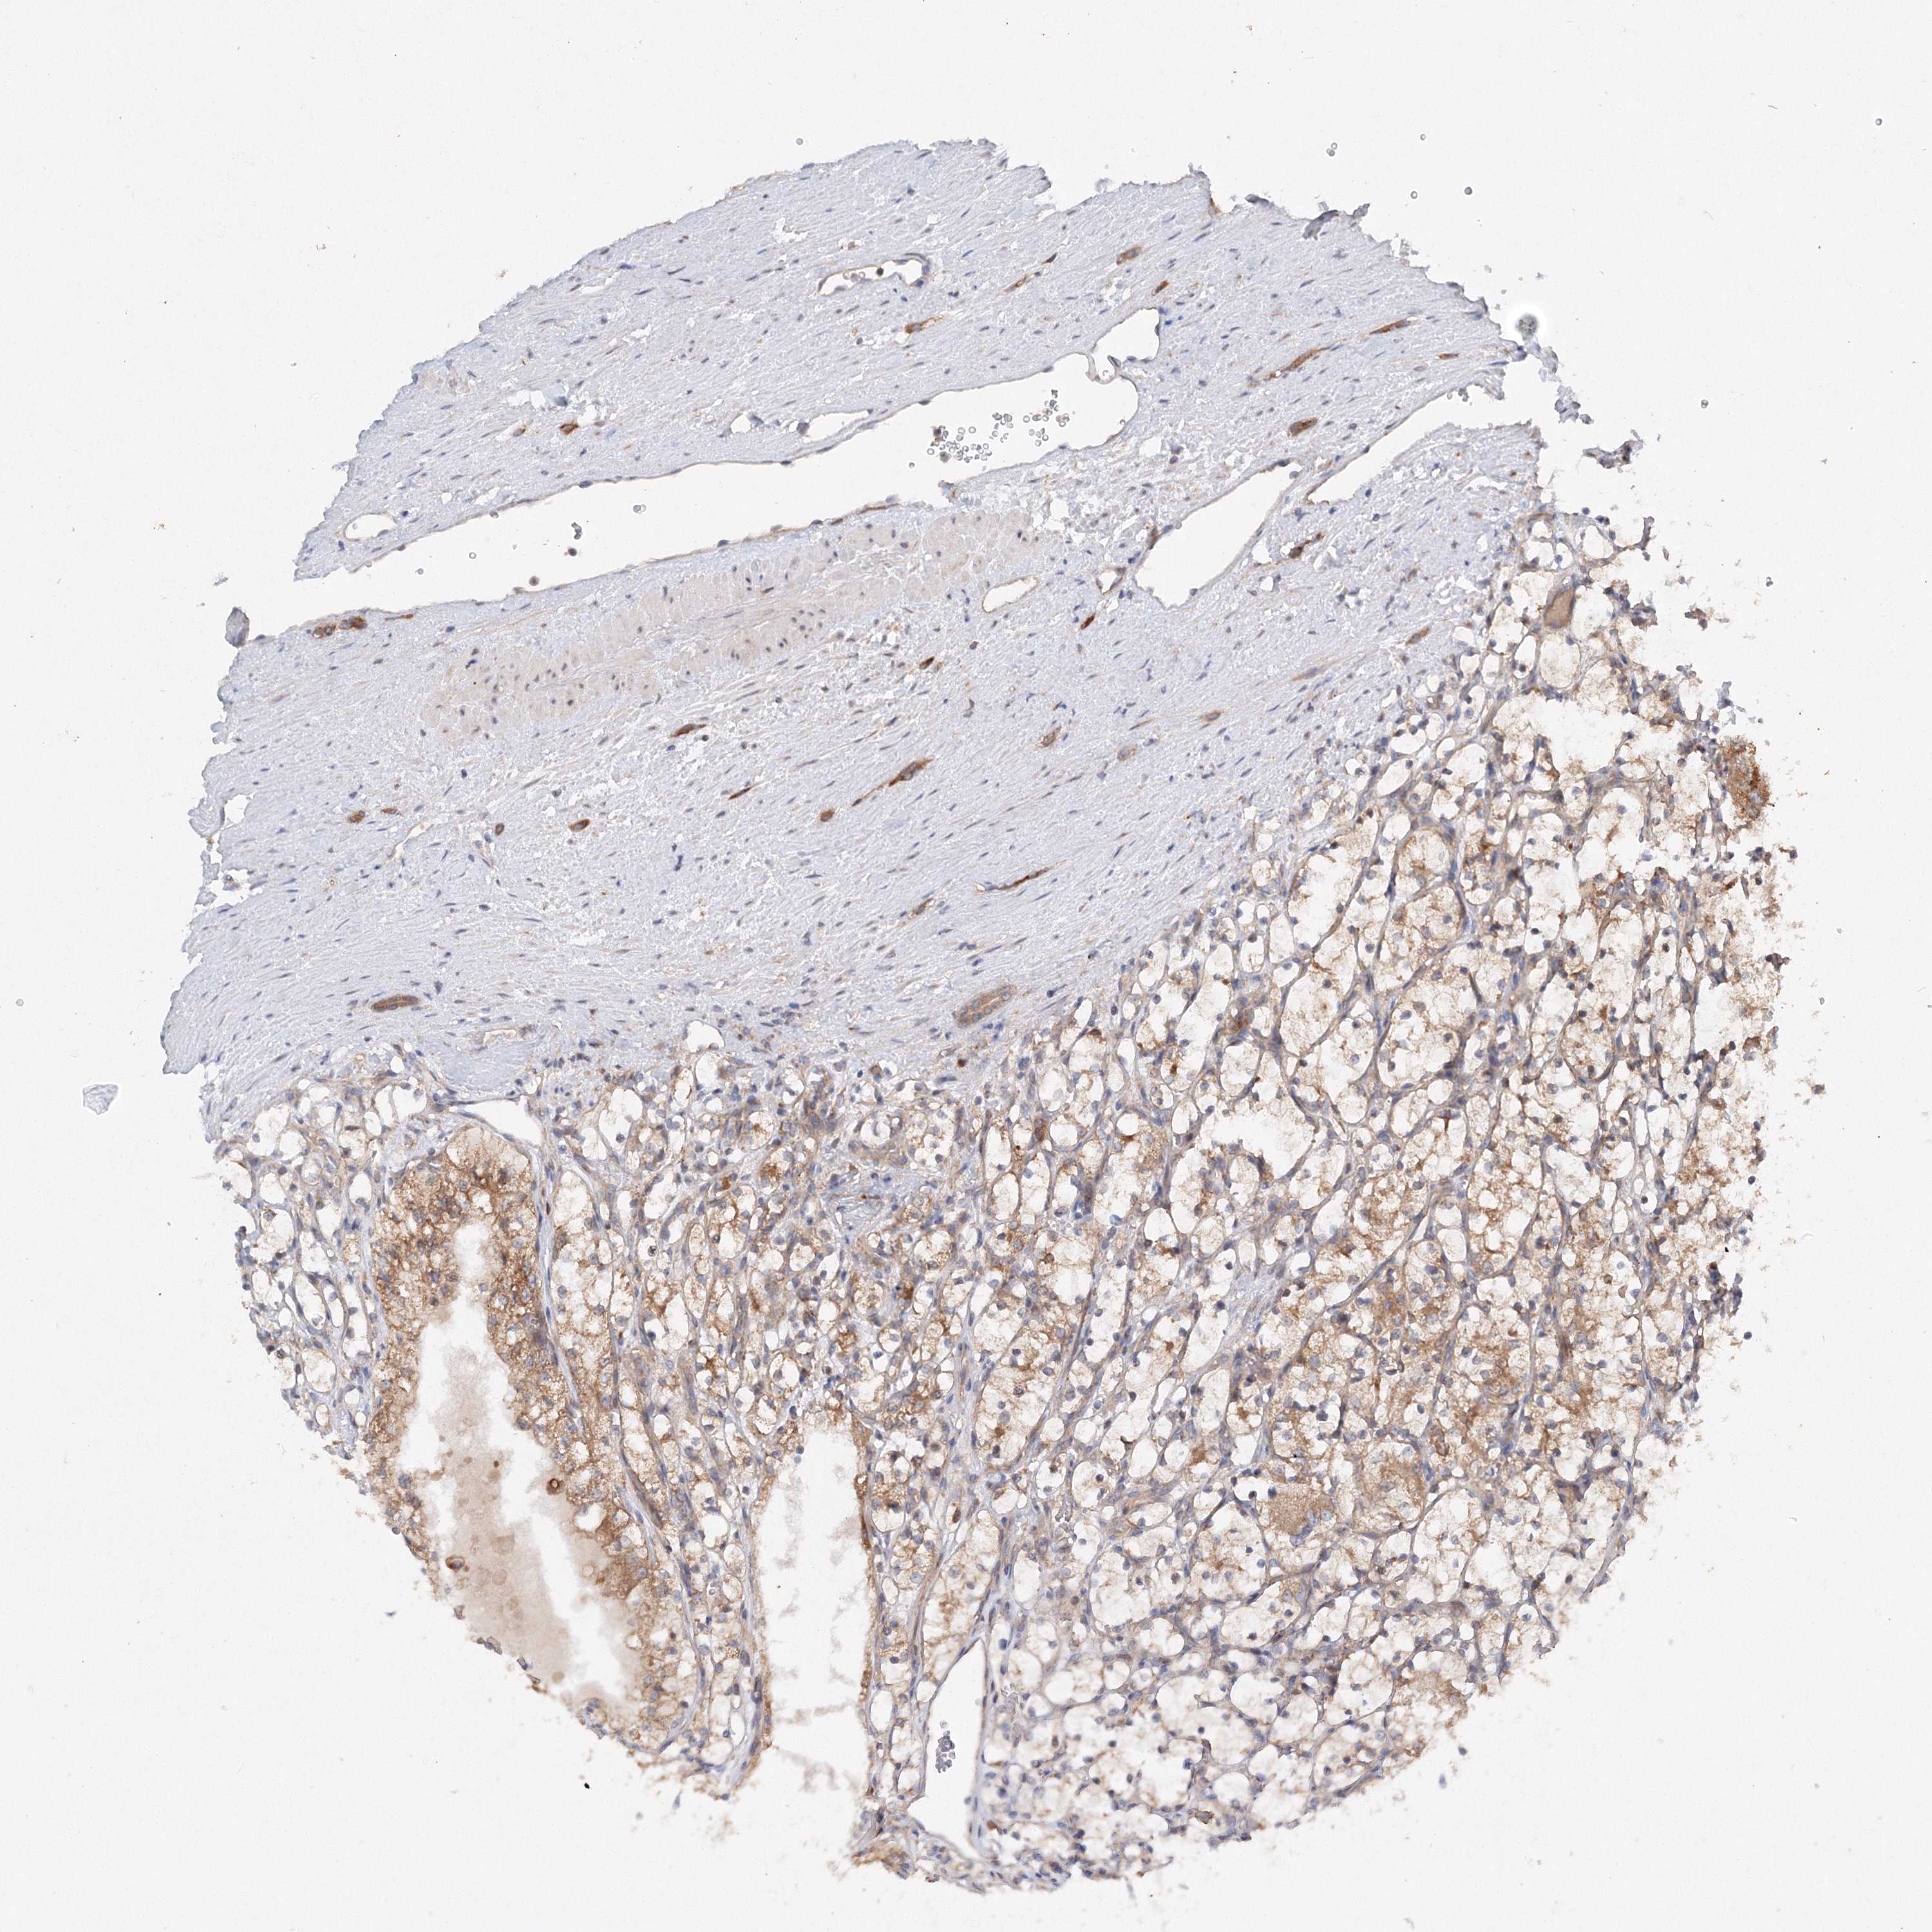

KIDNEY RENAL CLEAR CELL CARCINOMA (VALIDATION) - Interactive survival scatter ploti

The Survival Scatter plot shows the clinical status (i.e. dead or alive) for all individuals in the patient cohort, based on the same data that underlies the corresponding Kaplan-Meier plots. Patients that are alive at last time for follow-up are shown in blue and patients who have died during the study are shown in red.

The x-axis shows the expression levels (FPKM) of the investigated gene in the tumor tissue at the time of diagnosis. The y-axis shows the follow-up time after diagnosis (years). Both axes are complimented with kernel density curves demonstrating the data density over the axes. The top density plot shows the expression levels (FPKM) distribution among dead (red) and alive patients (blue). The right density plot shows the data density of the survived years of dead patients with high and low expression levels respectively, stratified using the cutoff indicated by the vertical dashed line through the Survival Scatter plot. This cutoff is automatically defined based on the FPKM cutoff that minimizes the p-score. The cutoff can be changed by dragging the vertical line or by entering a cutoff value in the square labeled "Current cut-off".

Under the Survival Scatter plot the p-score landscape (black curve; left axis) is shown together with dead median separation (red curve; right axis). Dead median separation is the difference in median mRNA expression between patients who have died with high and low expression, respectively. It is calculated as follows: median FPKM expression of dead patients with high expression - median FPKM expression of dead patients with low expression. This is intended to aid the user in visually exploring custom cutoffs and the associated p-scores and dead median separation.

Individual patient data is displayed and can be filtered by clicking on one or more of the category buttons on the top of the page. Categories describing expression level and patient information include: high, low, alive, dead, female, male and tumor stages. The scale of the x-axis can be toggled between linear and log-scale by clicking on the "x log" button. Mouse-over function shows TCGA ID, patient information and mRNA expression (FPKM) for each patient.

& Survival analysisi

Kaplan-Meier plots summarize results from analysis of correlation between mRNA expression level and patient survival. Patients were divided based on level of expression into one of the two groups "low" (under cut off) or "high" (over cut off). X-axis shows time for survival (years) and y-axis shows the probability of survival, where 1.0 corresponds to 100 percent.

SLC36A1 is not prognostic in Kidney Renal Clear Cell Carcinoma (validation)

Best expression cut offi

Based on the FPKM value of each gene, patients were classified into two groups and association between prognosis (survival) and gene expression (FPKM) was examined. The best expression cut-off refers the FPKM value that yields maximal difference with regard to survival between the two groups at the lowest log-rank P-value. Best expression cut-off was selected based on survival analysis .

When clicking on this number, the vertical dashed line indicating cut-off, the interactive survival plot, and the Kaplan-Meier curve will be adjusted to show results based on the best expression cut-off.

: 9.07

TCGA RNA samplesi

RNA-seq data is reported as average FPKM (number Fragments Per Kilobase of exon per Million reads), generated by the The Cancer Genome Atlas (TCGA) .

Normal distribution across the dataset is visualized with box plots, shown as median and 25th and 75th percentiles. Points are displayed as outliers if they are above or below 1.5 times the interquartile range. FPKM values of the individual samples are presented next to the box plot.

Average pTPM 9.8

Number of samples 100